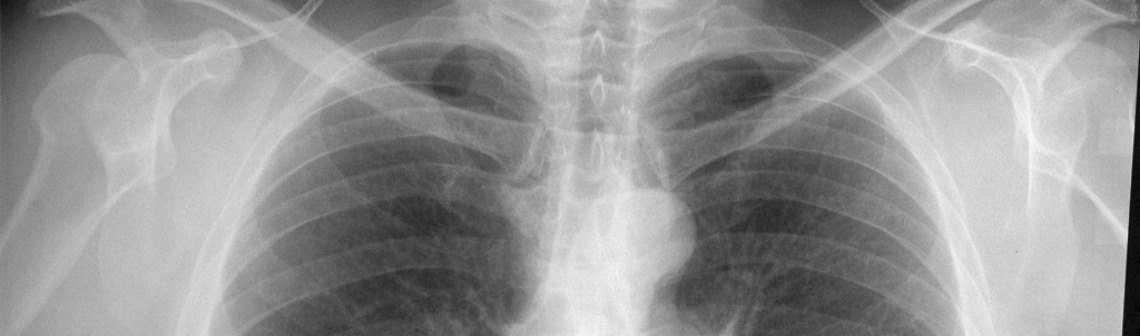

Mais cette fois-ci, le machine learning a été mis à profit d’une cause moins ludique : l’imagerie médicale. Tout a commencé dans le kibboutz de Shefayim entre Tel Aviv et Haifa. Ce kibboutz est connu comme étant extrêmement robuste financièrement, n’ayant eu besoin d’une aide financière lors de la crise de 1980. Dans cet environnement extrêmement technologique, la startup Zebra Medical Vision propose une application différente du machine learning : apprendre à un ordinateur à détecter une maladie en observant des images provenant d’imageries médicales conventionnelles. Et l’enjeu est de taille car l’entreprise estime que plus d’un milliard de personnes sont bénéficiaires des services d’imageries tels que l’IRM, les scanners X ou les scanners TEP. Cependant, pour le moment, toutes ces images produites ont besoin d’un spécialiste pour les analyser- et parfois simplement pour une vérification de routine ou pour des problèmes évidents comme un os cassé – ce qui entraîne naturellement une augmentation des frais médicaux.

Pour ‘apprendre’ à l’ordinateur à analyser ces images, des milliers d’images de patient-e-s déjà analysées par des spécialistes ont été chargées sur le programme. L’ordinateur utilisant un algorithme appelé Emphysema a donc appris à avoir le même résultat que le ou la radiologue. Finalement, cela revient un peu au même apprentissage que celui effectué par le ou la spécialiste durant sa formation où il ou elle apprend à reconnaître des ensembles de points qui semblent suspects dans une image. L’entreprise a fait le choix de s’intéresser en priorité aux os, au foie, aux poumons et au cerveau, combinant les trois techniques médicales évoquées ci-dessus.